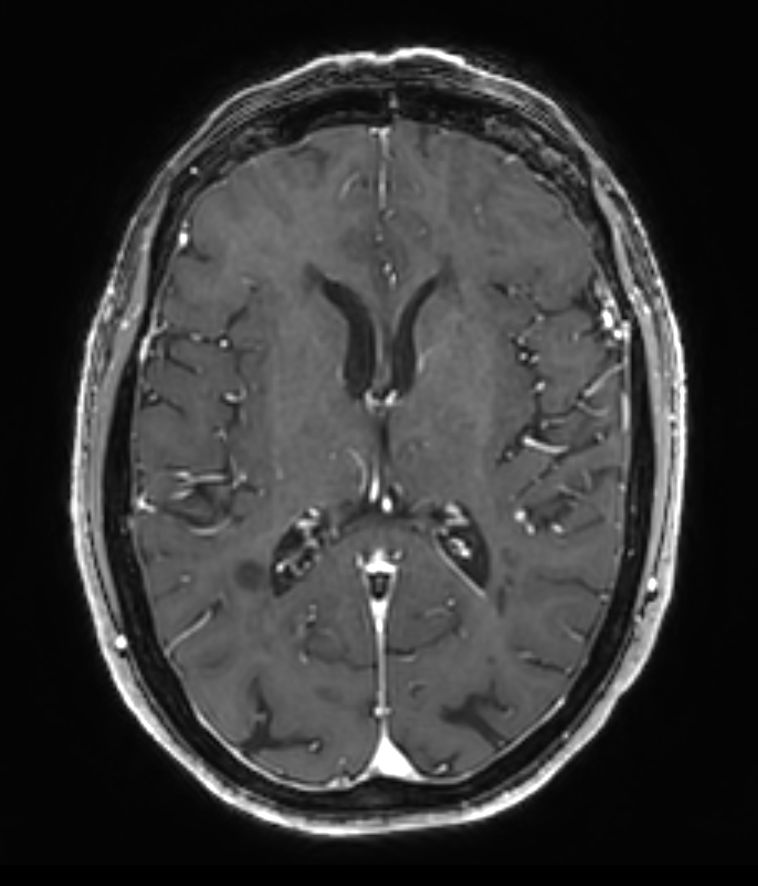

3D T1w FFE +Gado Compressed SENSE